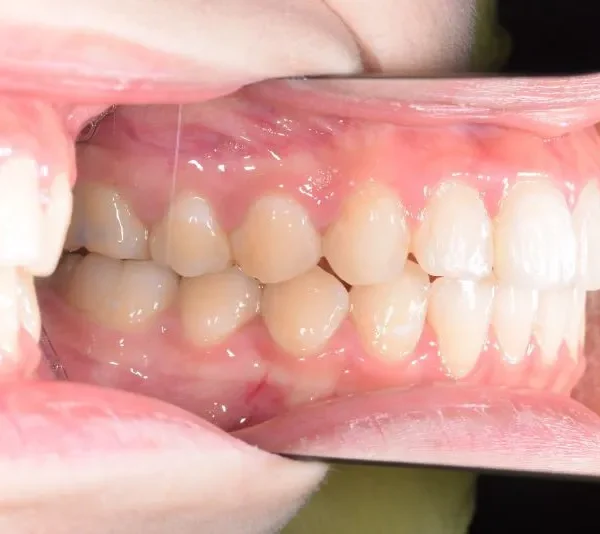

初診時年齢 19~29歳 (女性) 主訴 上下がガタガタ・出っ歯

診断名 叢生・上下顎前突 装置名

上下の歯並びがガタガタで口元が出ています。

元々小学生の時にマルチブラケット装置を上下につけ、矯正治療を受けていました。

何年か経過後、ガタガタと口元が気になると受診されました。

再治療の時は、上の歯は前から見えにくいオリジナル固定装置、下の歯はマルチブラケット装置を使用し、治療しました。